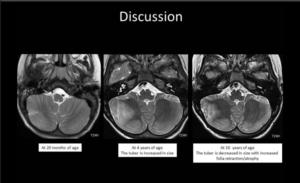

A 3-year-old child is admitted to the hospital due to decreased appetite and weight loss. She has been afebrile, and has not had vomiting or diarrhea.

Her activity level has decreased over the past two weeks.

She had been healthy until 2 months ago, when she was hospitalized for 48 ...

infection with mild respiratory distress and poor fluid intake.